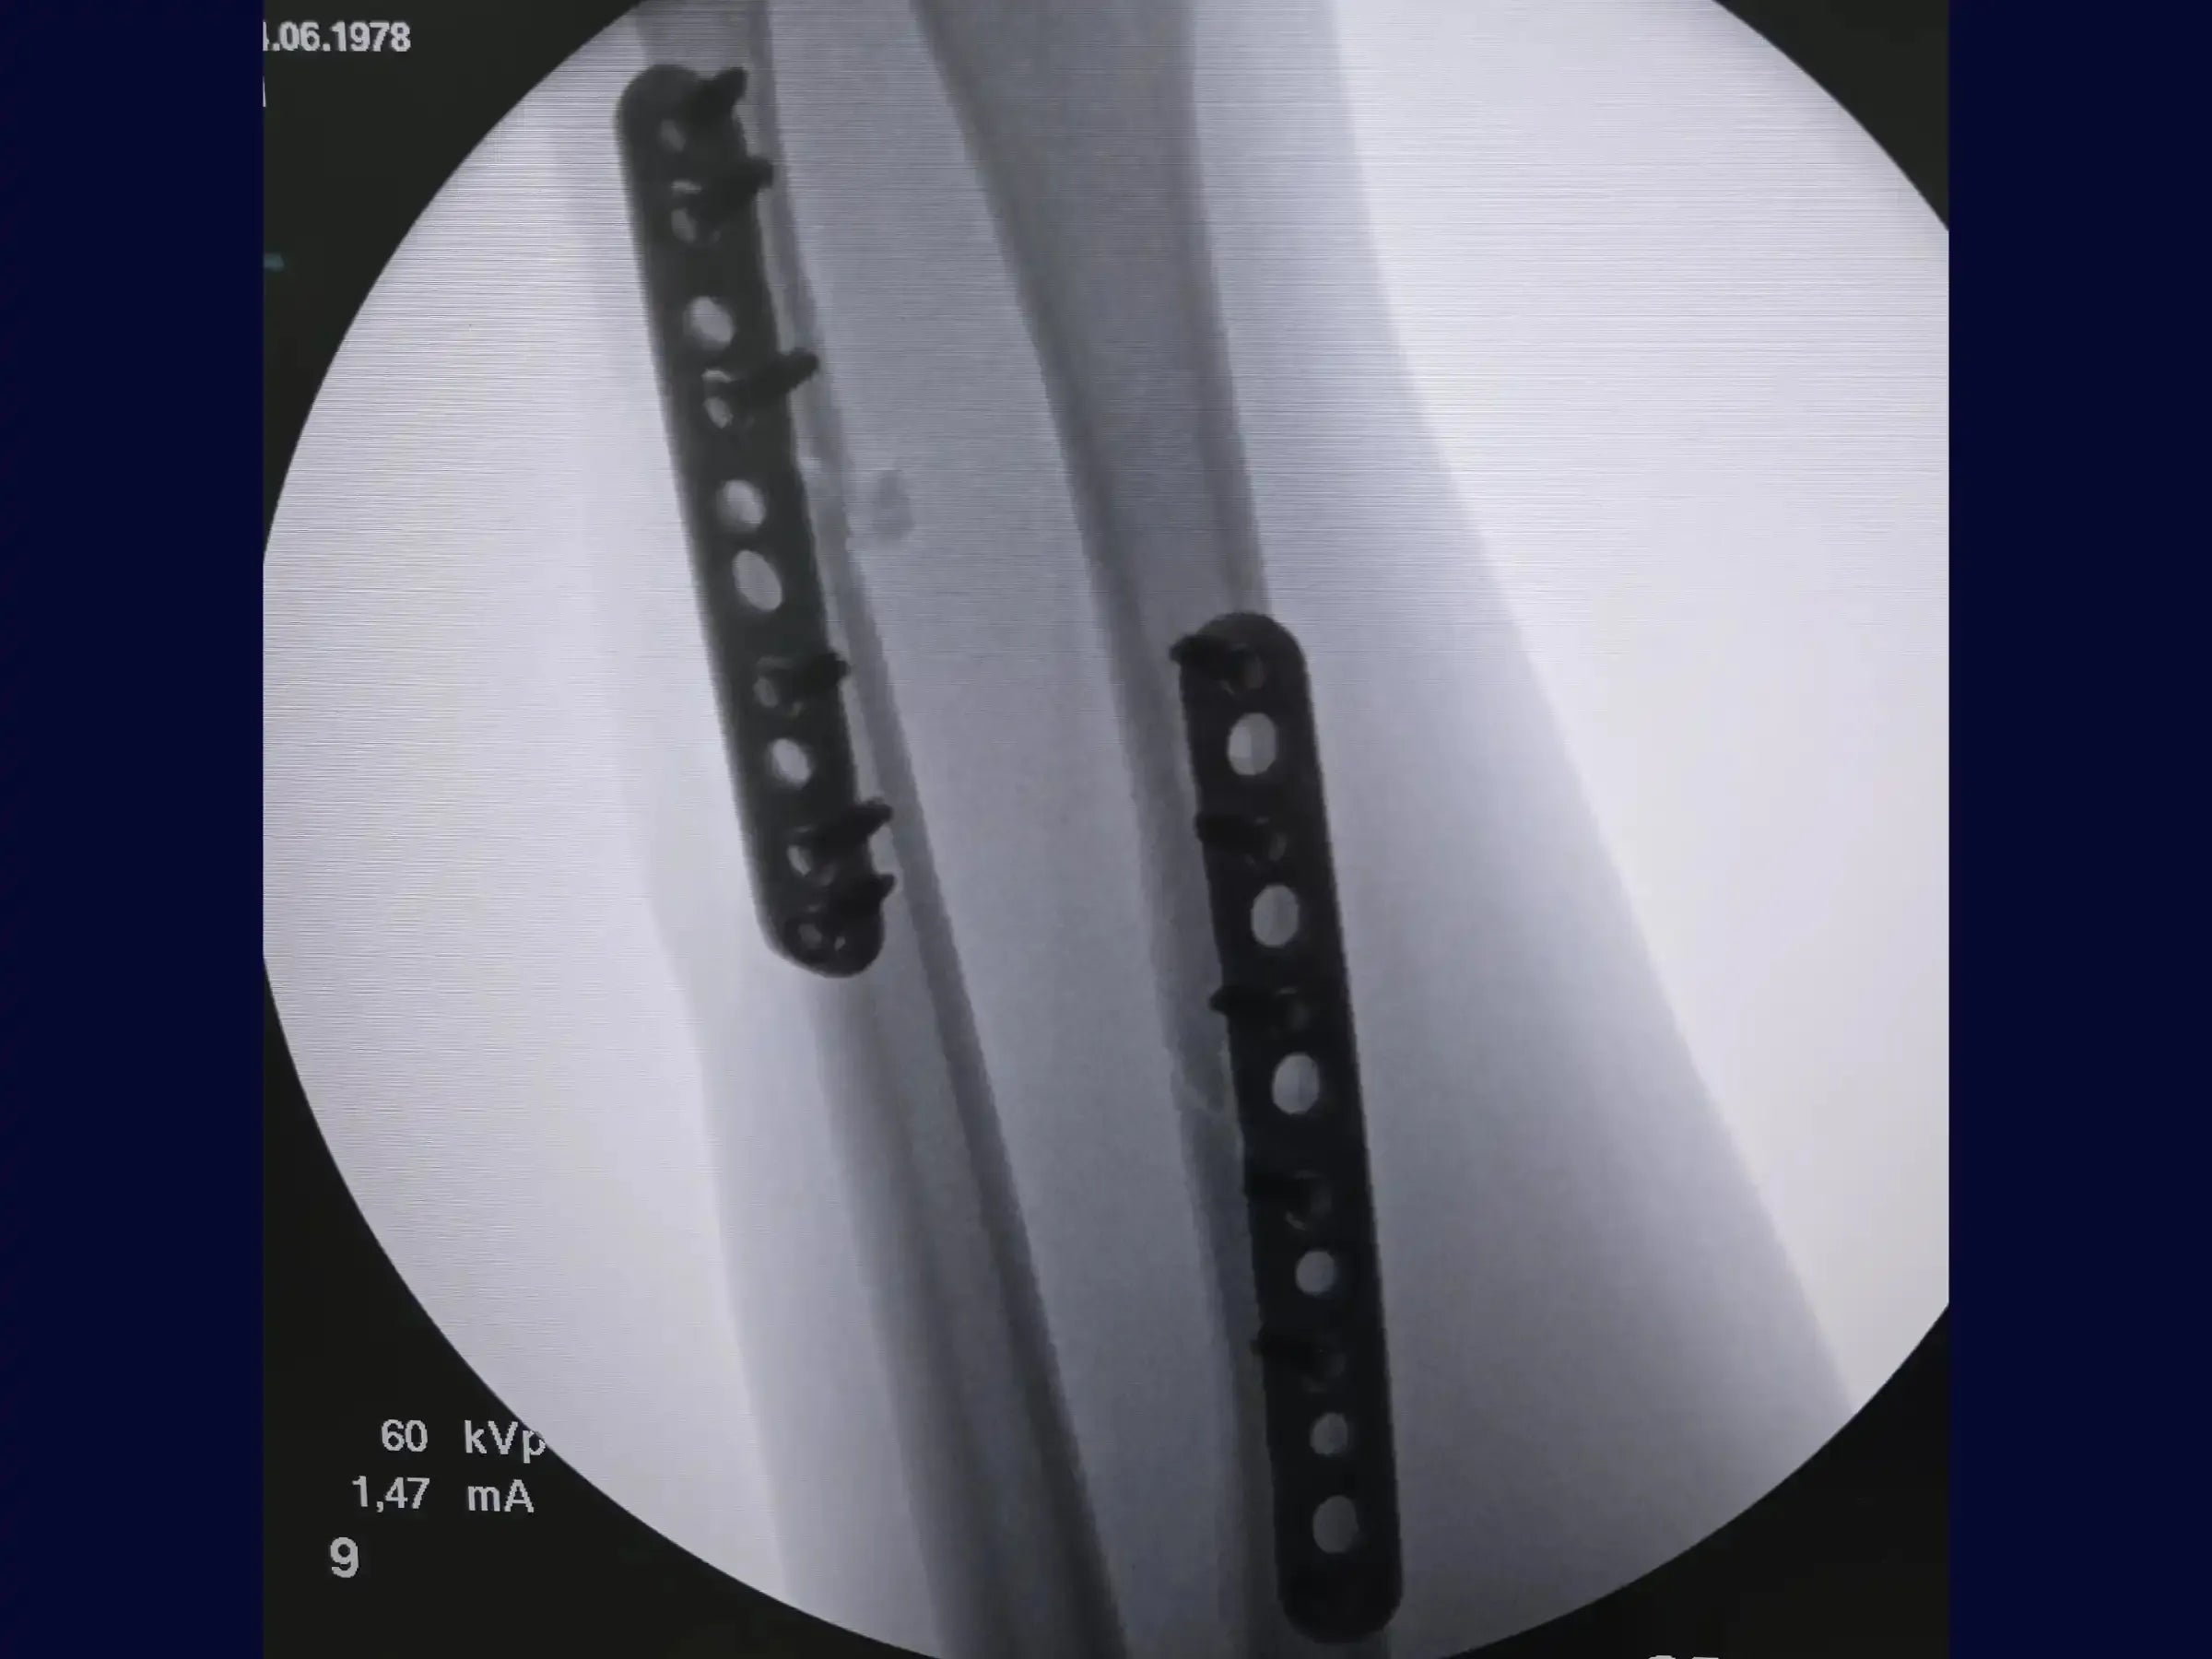

- Estabilização e Plaqueamento: Reposicione a pinça de redução distalmente para otimizar a manipulação. Com o rádio já estabilizado, alcance a redução da ulna para excelente estabilidade e alinhamento. Realize o pré-tensionamento da placa para evitar gap na cortical oposta e utilize uma placa DCP (Dynamic Compression Plate) bloqueada de 3.5 mm.